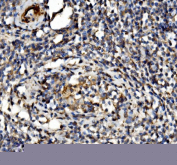

Immunohistochemical staining using EIF3D antibody on paraffin-embedded human testicular cancer tissue sections. Heat-induced epitope retrieval was performed using EDTA buffer (pH 8.0) prior to antibody incubation. Sections were blocked and incubated with EIF3D antibody overnight at 4C. Detection was carried out using an HRP-based secondary antibody with DAB as the chromogen. Staining shows cytoplasmic immunoreactivity in tumor cells. Nuclei were counterstained with hematoxylin.